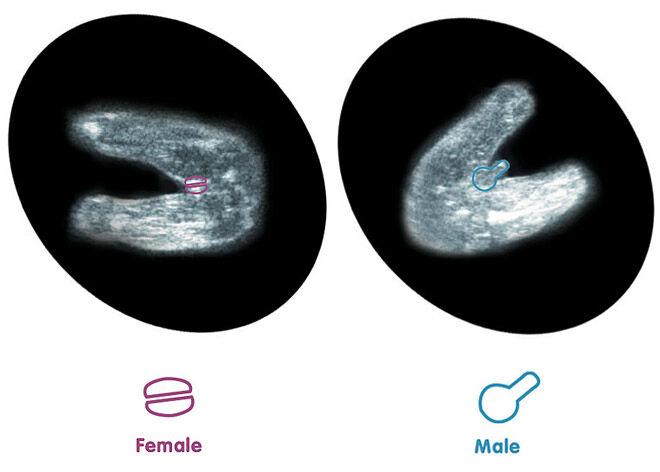

mindtastik.comHur Man “förutspår” Barnets Kön Från Ett Tidigt Ultraljud | Mum’s